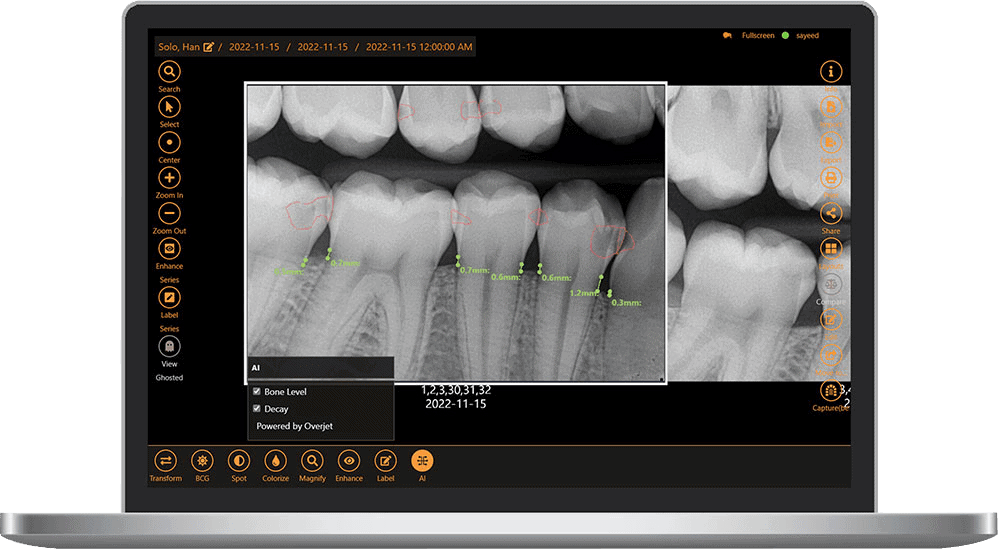

Embedded AI for X-ray Analysis

Leverage advanced AI overlays to improve diagnostic accuracy and consistency for dental professionals and help patients visualize areas of concern. With real-time FDA-cleared AI analysis, share more “a ha” moments with patients to increase case acceptance by up to 30% and submit insurance claims with confidence.

Advanced Toolset

Volume rendering, zoom, measurements, annotations, curved slice/pano reconstruction, implant planning, and nerve canal tracing.

Full Clinical Suite

Custom clinical filters and image enhancement tools, templates, bitewings & measurement tools to improve diagnostic accuracy.